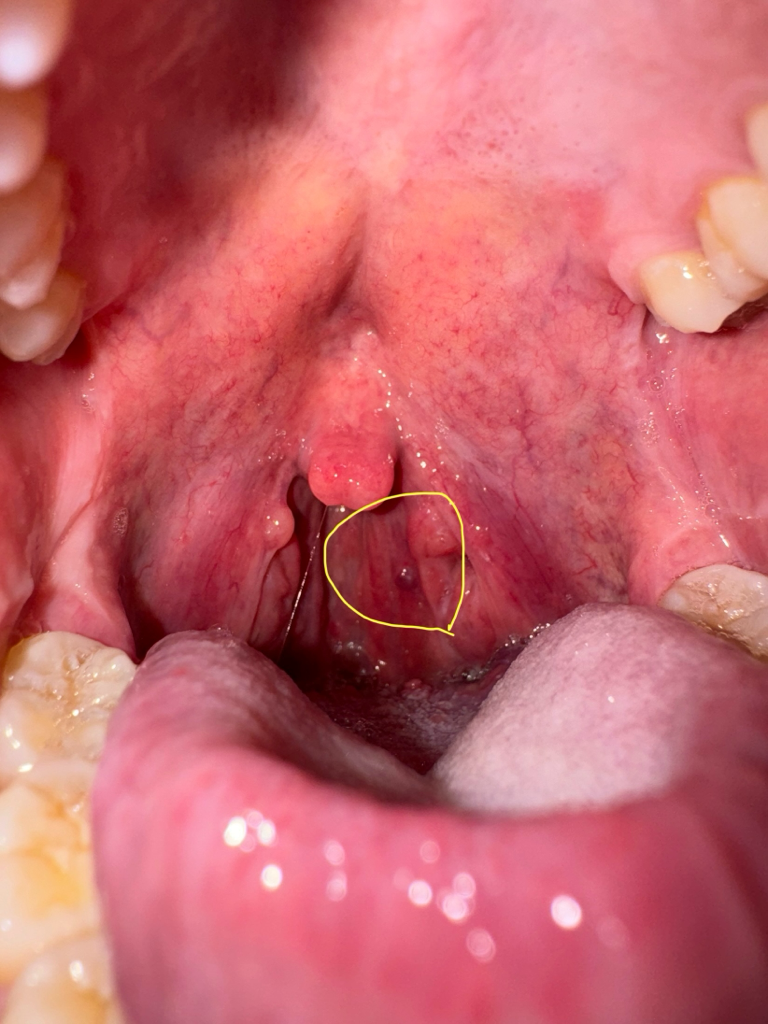

편도에 처음보는 혹이 있는데 색상이 이상합니다.. 단순 편도염일까요 편도암이나 다른 질병일까요?

평소에 편도 결석이 자주 끼긴했었는데, 편도에 이런게 생긴적은 처음입니다..

오늘 아침부터 침삼킬때 목이 아프더니, 지금은 귀도 같이 먹먹하네요.. 왼쪽 편도부분, 목을 눌렀을때는 당연히 아프구요..

몸이 살짝 늘어지긴 하지만, 몸살 증상은 없습니다. 열은 아직은 나지 않습니다. 36.7도로 정상체온 범주입니다.

편도염이 자주 생기긴 했었는데, 이처럼 한쪽만 아프고, 귀까지 먹먹한적은 처음인것 같아서 걱정입니다.

사진 첨부합니다.

염증이 심한 경우에 생긴 수포로 보입니다. 단순 염증이므로 너무 걱정마시고 이비인후과 진료보시는 것을 권유드립니다.